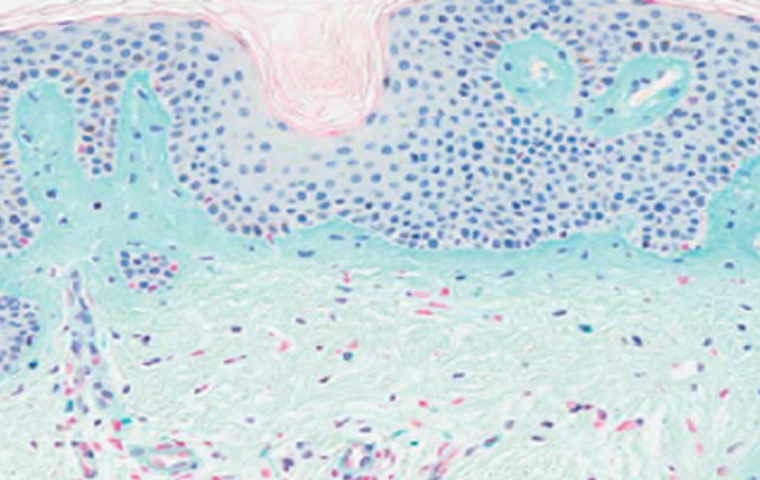

콜라겐 생성 촉진

시술 직후 볼륨감을 주고, 체내 콜라겐 생성을

유도해 효과가 오래 지속됩니다.

CaHA 입자분해

겔은 흡수되고 CaHA 입자는 자연 분해되어

최종적으로 내 콜라겐만 남습니다.